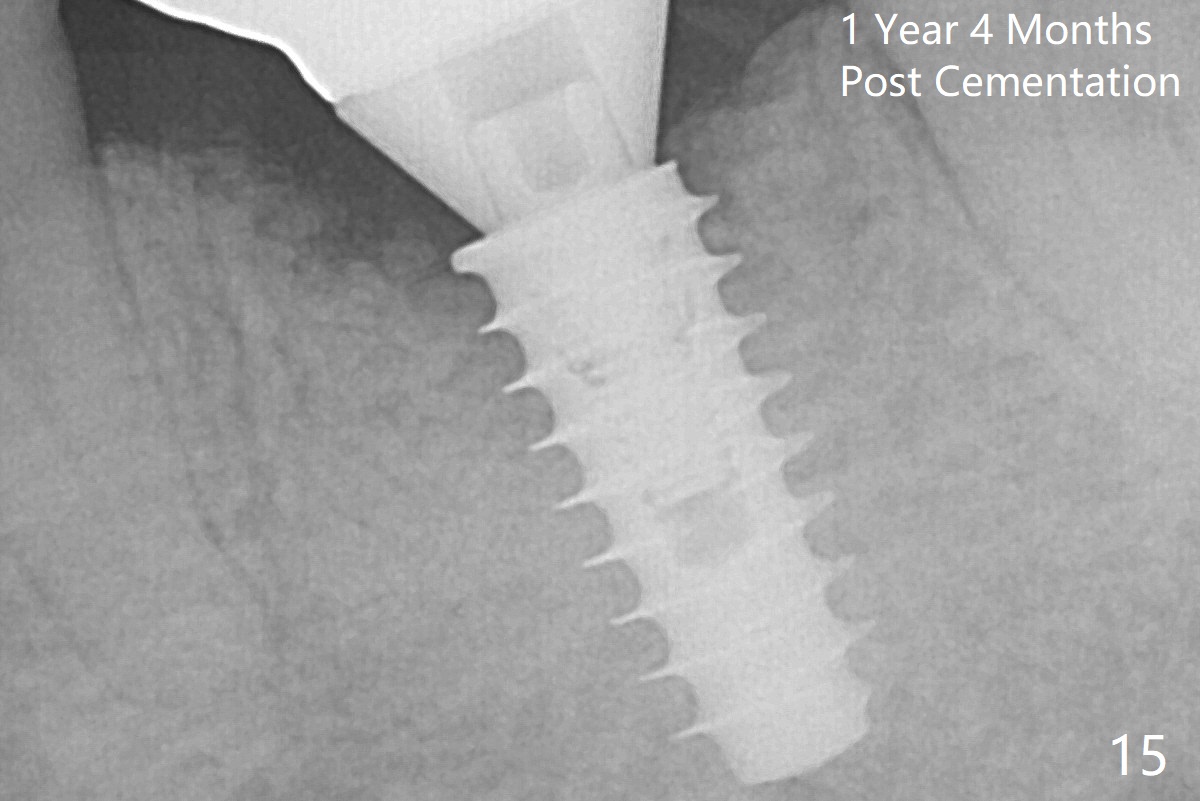

There is a new pattern of bony trabeculae around the implant 4.5 months postop (Fig.14). Bone density increases 1 year 4 months post cementation (Fig.15).